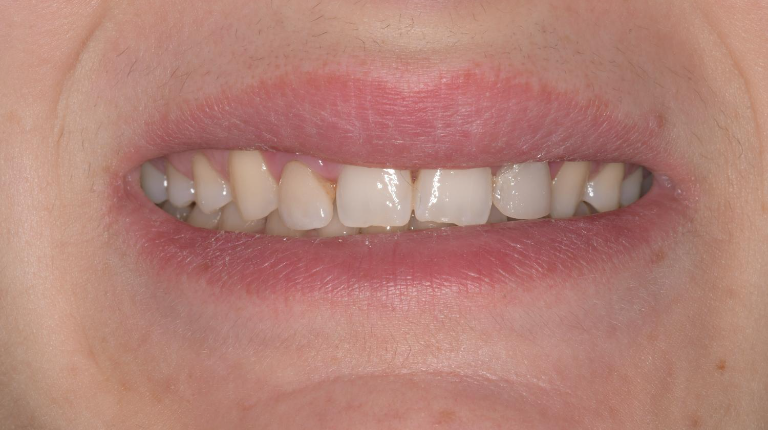

La paciente M. de 25 años, acude a mi consulta con mucha gana de arreglar sus dientes.

Me cuenta que ya en pasado, a los 18 años, se sometió a una ortodoncia y intentar enmascarar la microdoncia de los laterales con unas «carillas cerámicas». Esto era el resultado de dicho tratamiento:

La paciente rechazaba cualquier tipo de tratamiento ortodontico (por cansancio y porque trabaja cara al publico), tras mucho esfuerzo consigo convencerla a ponerse ortodoncia al menos en la arcada inferior para aprovechar de estos espacios para ganar resalte y corregir la sobre mordida y sobre todo poder generar una guía canina una vez completado el tratamiento restaurador.